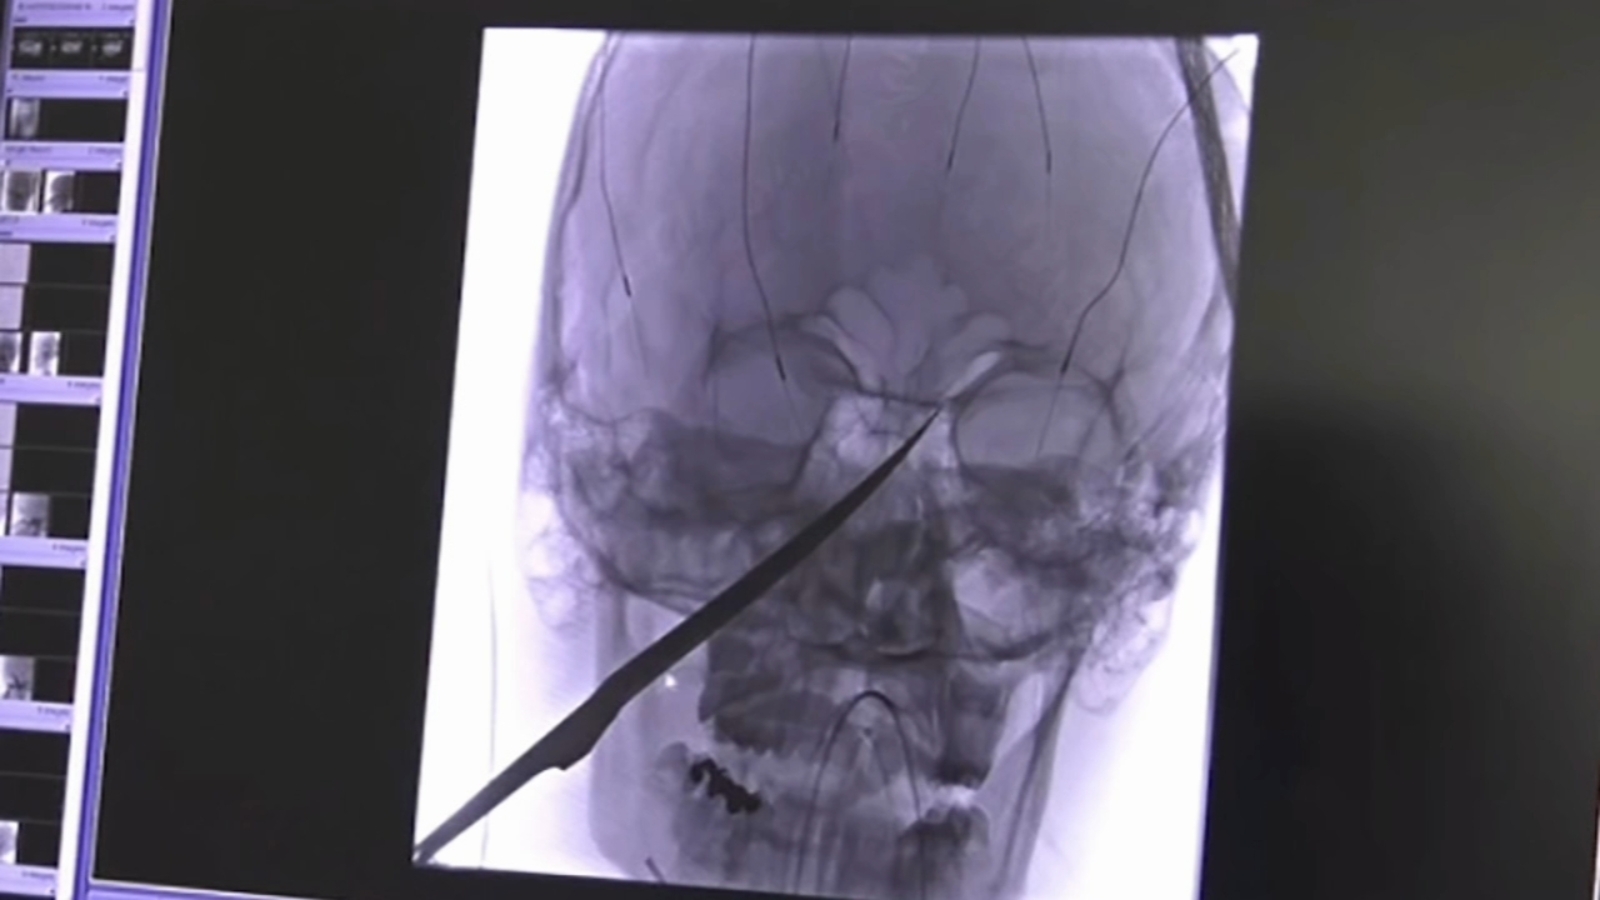

From www.foxnews.com

Kansas teen miraculously survives 10inch knife in face 'It was really Knife Face In Or Out the knife always goes on the right hand side, cutting edge facing in, and the dinner fork goes on the left hand side. the first and basic rule to get you started is: by kendell cronstrom. knives facing the wrong direction. Utensils are placed in the order of use; Forks (almost always) sit to the left. Knife Face In Or Out.

From abc7ny.com

Kansas teen Eli Gregg impaled in face by 10inch knife after falling on Knife Face In Or Out the knife should be positioned on the right side of the dinner plate, with the blade facing inward towards the plate. the first and basic rule to get you started is: utensils are set in order of use from the outside in. A second rule, with only a few exceptions, is: The blade should always face the. Knife Face In Or Out.